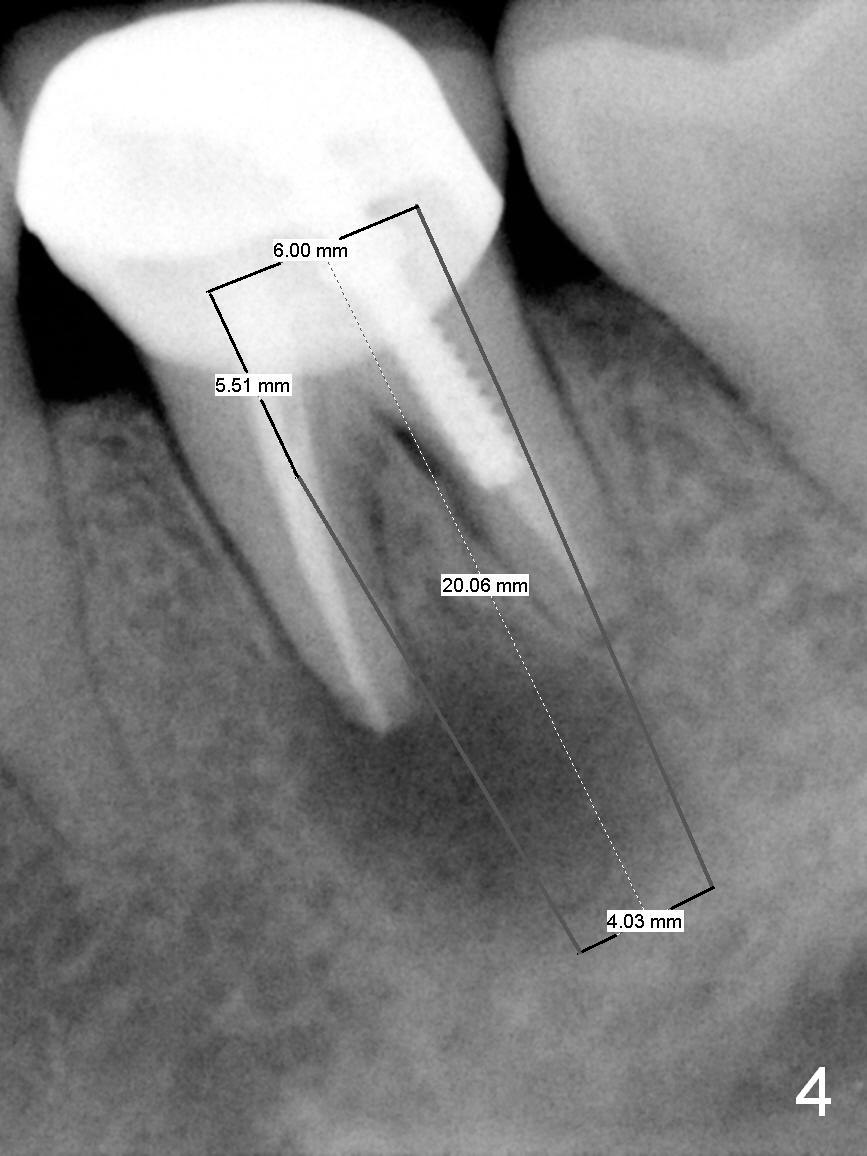

A 58-year-old lady has a long-standing periapical lesion with several episodes of acute infection (Fig.1-3, taken 10, 9 and 2 years ago, respectively). Explore the socket for size and wall integrity (Clindamycin). If the bony defect is not extensive, place a longest implant (18 mm bone-level, 20 mm tissue-level) with moderate diameter (5.5, 6 mm). Otherwise use a shorter, but wider tapered implant (7x12 mm (bone-level), 7 or 8x17 mm (tissue-level)). If the socket is extremely large, consider using 7 or 8 x20 mm cylindrical tissue-level implant. Use Bicon 2 mm pilot drill with extension to measure the socket depth and obtain 3-6 mm new bone or until 20 mm (gingival margin). Take PA. The 1st option is to use UF 3-4.7x18 mm drills at 50 RPM. Make sure that the depth is reached (septum crestal level) and check osteotomy wall integrity after each drill. Then place a 5 or 5.5x16 or 18 mm implant (Fig.6). The 2nd and 3rd options are shown in Fig.4 and 5. Due to severe infection and pain, a shorter implant is placed.